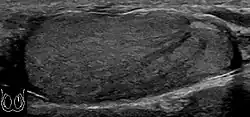

Fig. 29. Undescended testis. (a) Normal testis in the scrotum. (b) Atrophic and decreased echogenicity of the contralateral testis of the same patient seen in the inguinal region.